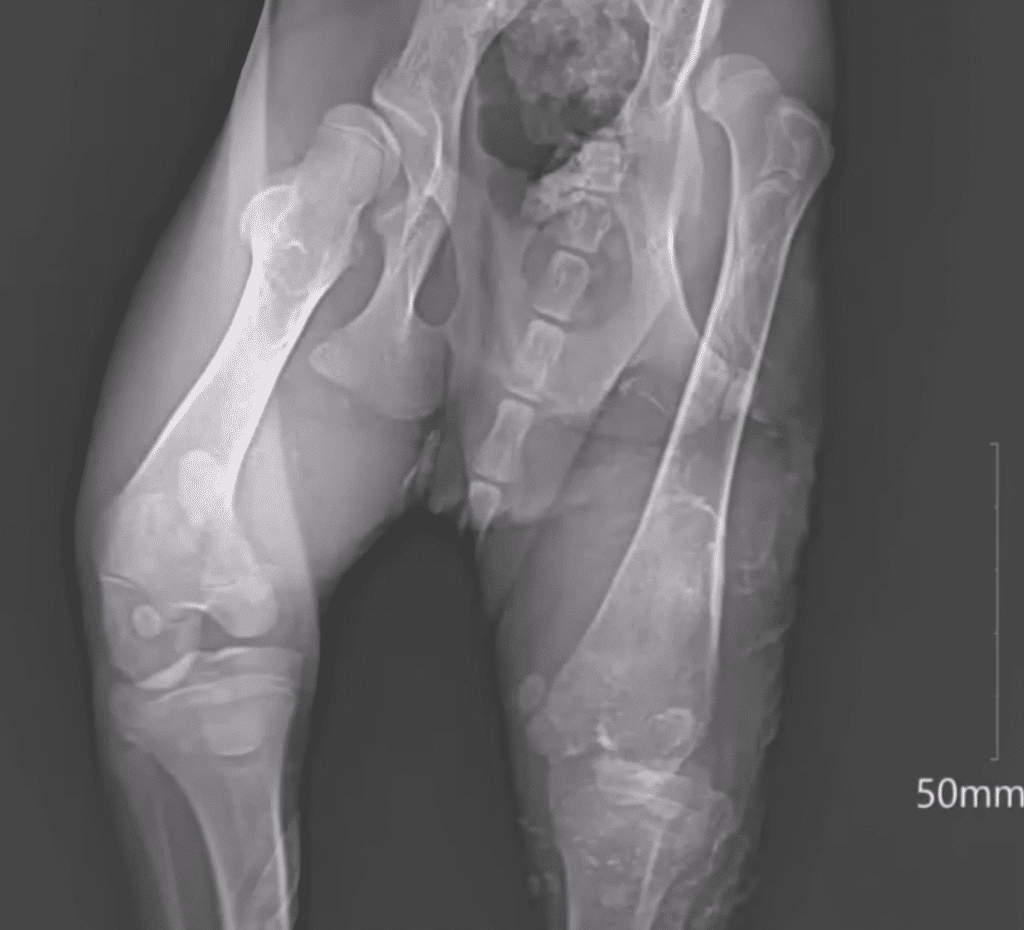

A Body That Needed Time to Heal

At the clinic, his condition told a quiet story of hardship.

Old injuries.

A body that had adapted to survive.